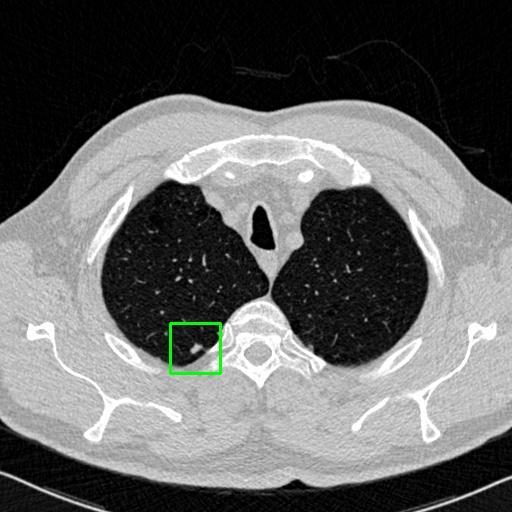

We developed an AI-based system using deep learning models for analyzing lung CT scans to detect and classify pulmonary nodules. We chose the YOLOv11 architecture for its enhanced object detection capability and adapted it specifically for medical imaging, incorporating pixel-level precision and severity classification.

Classification into three severity levels with colored bounding boxes.

Successfully built and deployed an AI model (YOLOv11) capable of detecting lung nodules in CT scans with high accuracy and real-time performance.

Designed a severity classification system that categorizes nodules into null, moderate, and severe using colored bounding boxes, assisting in rapid clinical decision-making.